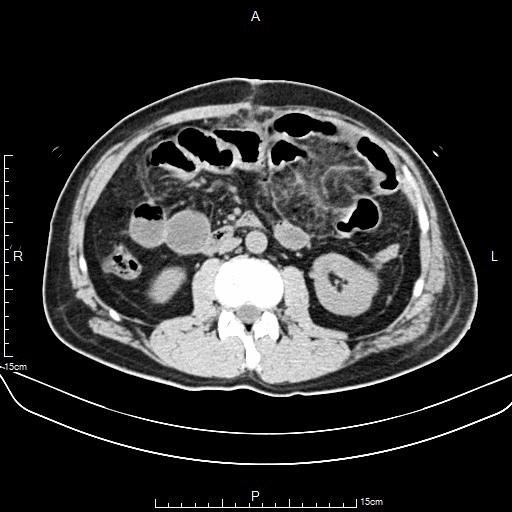

上腹部CT

下腹部CT